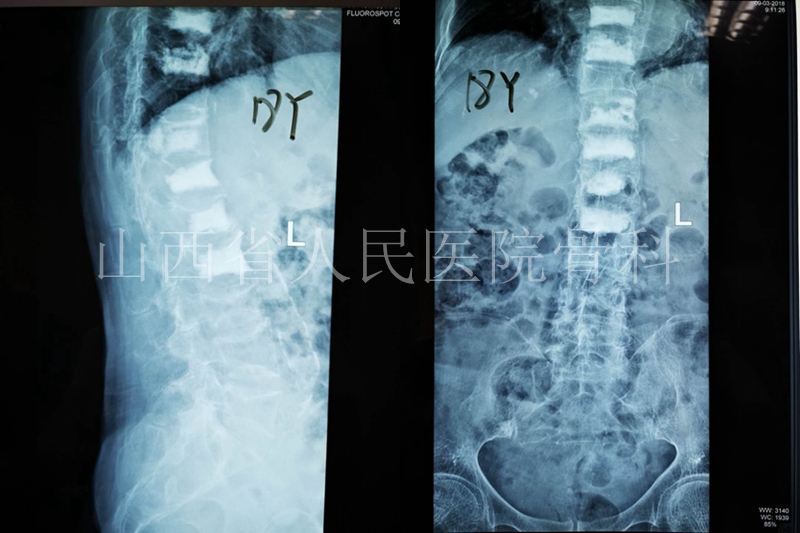

术后患者剧痛减轻,可是仍有隐痛,时隔3年,2016年患者再发T9压缩骨折,我们这次对其进行了新鲜+陈旧压缩骨折治疗。

2016年2月对新发的T9、T12、L1、L2椎体行PKP治疗